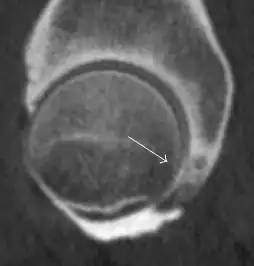

Most of the angles and measurements described in the plain radiograph section can be accurately reproduced on MRI. In addition, the superiority of MRI resolution with intra-articular contrast allows detection of labral and chondral abnormalities that may influence the choice of medical, percutaneous, or surgical management (Figure 9).[1]

Figure 9:

-

Sagittal T1 weighted image showing anterosuperior labral tear.[1] -

Sagittal T1 weighted image showing chondral lesion.[1] -

Sagittal CT-arthrography showing posteroinferior chondral injury.[1] -

Coronal CT-arthrography (d) showing ligamentum teres tear.[1]

MR arthrography has proven superior in accuracy when compared to native MR imaging. It is considered the best technique to assess the labrum. Knowledge of the normal variable morphology of the labrum helps to differentiate tears from normal variants. A triangular shape is most commonly seen in 66% of asymptomatic volunteers, but round, flattened, and absent labra can also be found in asymptomatic populations. MR arthrography has demonstrated sensitivity over 90% and specificity close to 100% in detecting labral tears. Loose bodies are demonstrated as filling defects surrounded by the hyperintense gadolinium.[1]

Association between labral tears and chondral damage has been demonstrated. This underscores the interaction between cartilage and labrum damage in the progression of osteoarthritis. Chondral damage to the posteroinferior part of the acetabulum as a contrecoup lesion occurs in approximately one-third of pincer cases secondary to persistent abutment on the anterior part of the joint leading to a slight posteroinferior subluxation. This is considered a bad prognosis sign.[1]

MR arthrography can also demonstrate ligamentum teres rupture or capsular laxity, which are debated causes of microinstability of the hip. Elongation of the capsule or injury to the iliofemoral ligament or labrum may be secondary to microtrauma in athletes. MR can demonstrate abnormalities in these cases, such as increased joint volume or a ligamentum teres tear (Figure 9).[1]

In synovial proliferative disorders, MRI demonstrates synovial hypertrophy. In the case of PVNS, characteristic foci of low signal intensity related to hemosiderin deposition are better seen on gradient echo T2* images (Figure 7). In the case of synovial osteochondromatosis, the synovial hypertrophy is accompanied by intermediate signal cartilaginous loose bodies and/or low signal calcified loose bodies.[1]

Due to the submillimeter resolution of MDCT arthrography, many authors consider this technique complementary to MR arthrography. It may even have superior sensitivity in detecting cartilage pathology, but lesser detecting labral tears.[1]